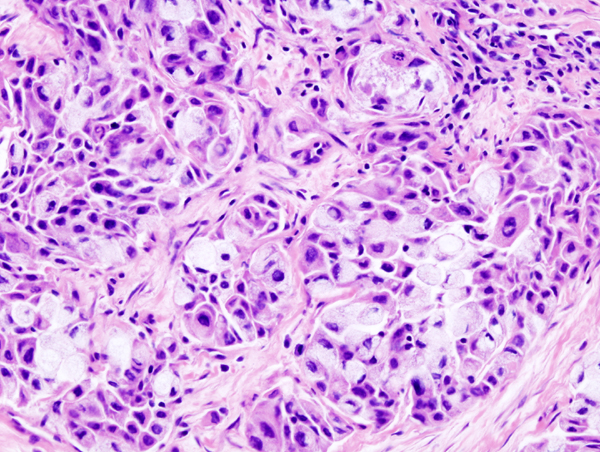

Mucoepidermoid Carcinoma

Mucoepidermoid carcinoma is a malignant tumor made up of squamous and mucin-producing cells.

Mucoepidermoid carcinoma is the most common malignant tumor of the salivary gland.

Mucoepidermoid carcinoma often occurs in the parotid.

The facial nerve is frequently compromised by mucoepidermoid carcinoma.